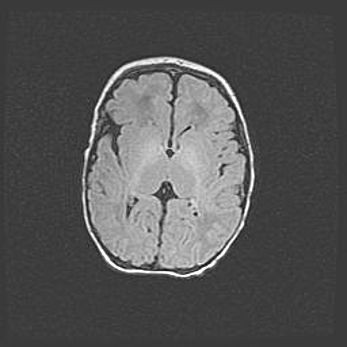

Сообщающаяся гидроцефалия. Кистозная энцефаломаляция головного мозга.

Возраст: 3 месяца 4 дня

Вес: 3100 г

Пол: женский

Окружность головы: 34 см

Срок гестации: 31 неделя

Кистозная энцефаломаляция головного мозга - одна из форм поражения головного мозга в детском возрасте. Характеризуется возникновением множественных и распространённых кист в коре, белом веществе и подкорковых образованиях головного мозга у плодов, новорождённых и детей раннего возраста. Развитие кистозной энцефаломаляции связано с внутриутробной асфиксией и гипотонией, родовой травмой, тромбозом синусов, пороками развития сосудов, инфекциями, сепсисом и другими причинами. Наиболее значимые инфекционные агенты: вирусы простого герпеса, цитомегалии, краснухи, токсоплазмы, энтеробактерии, золотистый стафилококк и другие.